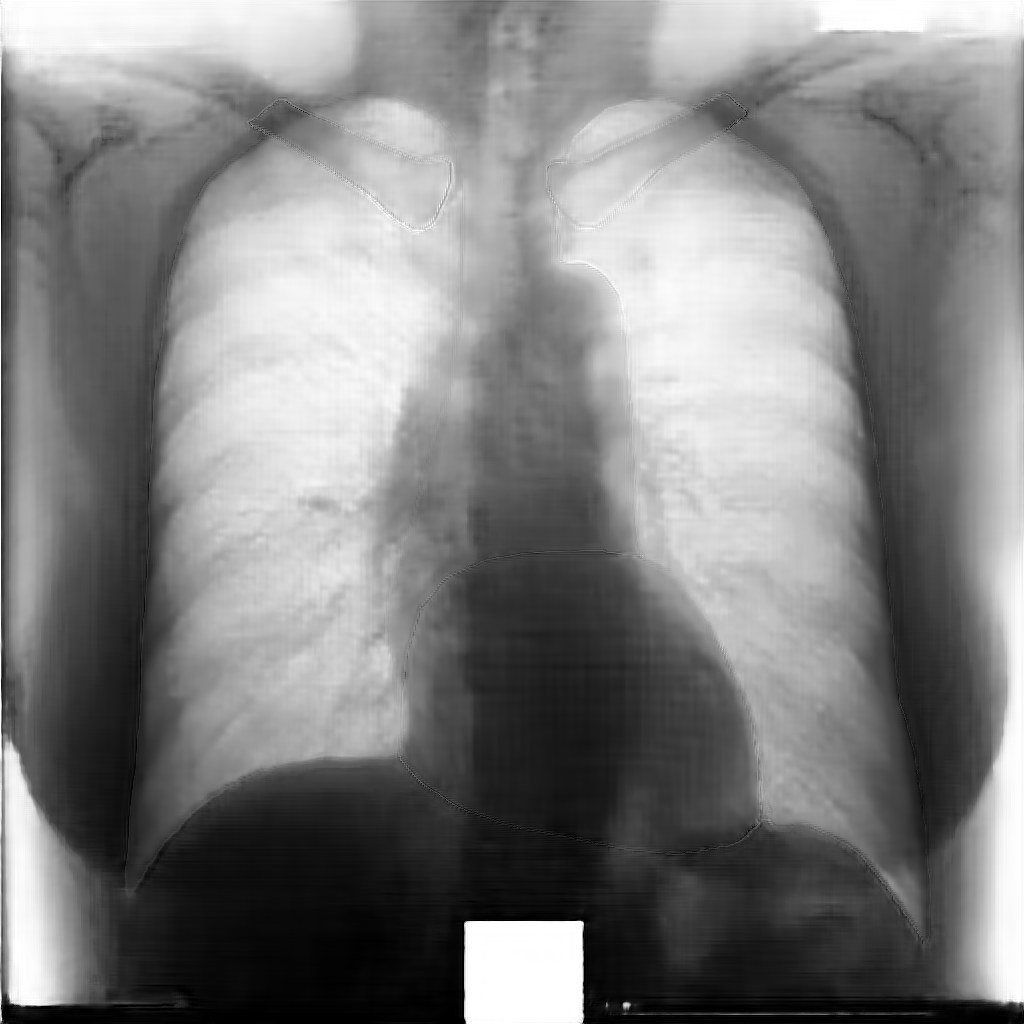

Chest radiographs are provided by the Japanese Society of Radiological Technology (JSRT) database [64]. The JSRT database comprises 247 CXRs and includes images with and without lung nodules. All images have a resolution of pixels and a spatial resolution of .175 mm/pixel, with 12 bit gray levels. Instead, segmentation supervisions for the JSRT database are available in the Segmentation in Chest Radiographs (SCR) dataset [6]. More precisely, this dataset provides chest X–ray supervisions which correspond with the pixel–level positions of the different anatomical parts. Such supervisions were produced by two observers who segmented five objects in each image: the two lungs, the heart and the two clavicles. The first observer was a medical student and his segmentation was used as the gold standard, while the second observer was a computer science student, specialized in medical imaging, and his segmentation was considered that of a human expert.